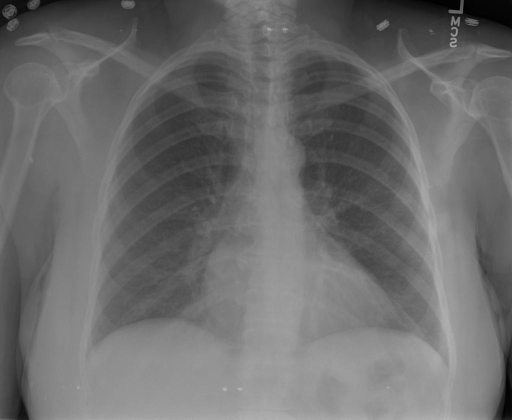

## 本文贡献 ![](./assets/images/xrayglm.png) - 借助ChatGPT以及公开的数据集,我们构造了一个`X光影像-诊断报告`对的医学多模态数据集; - 我们将构建的中文胸部X光片诊断数据集在[VisualGLM-6B](https://github.com/THUDM/VisualGLM-6B)进行微调训练,并开放了部分训练权重用于学术研究; ## 数据集 - [MIMIC-CXR](https://physionet.org/content/mimic-cxr-jpg/2.0.0/)是一个公开可用的胸部X光片数据集,包括377,110张图像和227,827个相关报告。 - [OpenI](https://openi.nlm.nih.gov/faq#collection)是一个来自印第安纳大学医院的胸部X光片数据集,包括6,459张图像和3,955个报告。 在上述工作中,报告信息都为非结构化的,不利于科学研究。为了生成合理的医学报告,我们对两个数据集进行了预处理,并最终得到了可以用于训练的**英文报告**。除此之外,为了更好的支持中文社区发展,借助ChatGPT的能力,我们将英文报告进行了中文翻译,并最终形成了可用于训练的数据集。 |数据集|数量|下载链接| |:-|:-|:-| |MIMIC-CXR-zh|-|-| |OpenI-zh|6,423|[诊疗报告(英文)](./data/openi-en.json)、[诊疗报告(中文)](./data/Xray/openi-zh.json) 、[X光影像](https://pan.baidu.com/s/13GBsDMKf6xBZBSHpoWH_EA?pwd=k9sh)| ## 快速上手 1. 安装环境 ```bash # 安装依赖 pip install -r requirements.txt # 国内换源安装依赖 pip install -i https://mirrors.aliyun.com/pypi/simple/ -r requirements.txt ``` 此时默认会安装`deepspeed`库(支持`sat`库训练),此库对于模型推理并非必要,同时部分`Windows`环境安装此库时会遇到问题。 如果想绕过`deepspeed`安装,我们可以将命令改为: ```bash # 安装依赖 pip install -i https://mirrors.aliyun.com/pypi/simple/ -r requirements_wo_ds.txt # 安装SwissArmyTransformer pip install -i https://mirrors.aliyun.com/pypi/simple/ --no-deps "SwissArmyTransformer>=0.3.6" ``` 2. 模型推理 |模型权重|下载链接| |:-|:-| |checkpoints-XrayGLM-300|-| |checkpoints-XrayGLM-3000|-| CLI推理: ```python python cli_demo.py --from_pretrained checkpoints/checkpoints-XrayGLM-3000 --prompt_zh '详细描述这张胸部X光片的诊断结果' ``` 更多[参数](https://github.com/WangRongsheng/XrayGLM/blob/main/cli_demo.py#L16) ## 效果展示 影像诊断: |X光影像|诊疗报告(医生)|XrayGLM| |:-|:-|:-| |![](./data/Xray/2_1.png)|根据X射线图像,心脏大小正常,肺部看起来很清晰。已经排除了肺炎、积液、水肿、气胸、腺病、结节或肿块的存在。该发现表明一切正常。换句话说,总体印象是胸部正常。|X光片显示,心脏大小正常。肺部没有气胸或胸腔积液的证据。骨骼结构看起来没有任何异常。总的来说,X光片表明没有发现急性心肺疾病的迹象。| |![](./data/Xray/2882_1.png)|X光图片显示没有扭曲的区域、可疑的骨质不透明度或胸腺积液。心脏大小轻微增大,但非常稳定。此外,没有气胸的证据,肺野也正常。总体来说,X光片显示没有急性心脏异常,但要注意轻微的心脏扩大。|X光片显示,心脏大小正常。肺部和纵隔轮廓清晰,没有气胸或胸腔积液的证据。骨骼结构完整,没有任何急性异常。| |![](./data/Xray/2577_1.png)|心影形态在正常范围内。没有急性骨质异常。有可能出现没有明显的吸水或肺实质状况的线索。没有大面积积液或气胸。有可能怀疑其有误吸或肺实质问题。为了确诊和治疗,可能需要进行适当的影像学随访。|心脏大小正常,肺部和纵隔轮廓清晰。没有急性异常或活动受限的证据。没有任何明显的气胸、胸腔积液或肺不张的迹象。此外,也没有发现任何局灶性骨质异常或其他急性疾病。| 多轮对话: |X光影像|诊疗报告(医生)| |:-|:-| |![](./data/Xray/861_1.png)|右侧主动脉突出观察到。心脏大小正常。胸部未发现明显的肺气肿、胸膜积液或可疑的肺部病变。报告指出已知右侧主动脉情况正常。| ```bash >> X光影像路径:./data/Xray/861_1.png >> 用户:这是一张什么图? >> XrayGLM:这张图片显示的是一张肺部检查的X光片。 >> 用户:请描述这张胸部X光片的诊断结果 >> XrayGLM:心脏大小正常,肺部清晰。没有急性心肺疾病的证据。 >> 用户:是否存在肺气肿? >> XrayGLM:没有肺气肿。心脏大小正常,肺部清晰。没有发现急性心肺疾病的证据。 >> 用户:平时饮食该注意什么? >> XrayGLM:饮食应该健康,均衡。建议增加蛋白质的摄入量,因为蛋白质有助于维持肌肉和骨骼的健康。多食用蔬菜、水果、全谷物以及健康的脂肪来源如橄榄油、鱼类等可以帮助获得足够的维生素和矿物质。此外,避免过度饮酒或吸烟,这些习惯可能会对心脏健康产生负面影响。 ``` ## 未来展望 1. 模型的能力更多来源于数据的支持,`OpenI-zh`作为微调数据集,其数据量足以支持研究,在更广泛的任务和性能表现上,我们认为**在大规模数据集上预训练并在高质量少量数据集上微调是一种可行的方案**; 2. 普遍意义的理解上,视觉多模态模型=视觉模型+语言模型。除了需要关注视觉模型信息与语言模型输出的搭配外,还需要**额外关注到语言模型的加强,在人机的对话中,尤其是医疗语言模型的问答上,除了专业的医疗问题回答,带有人文情怀的有温度的回答更应该是我们追寻的目标**。 ## 项目致谢 1. [VisualGLM-6B](https://github.com/THUDM/VisualGLM-6B)为我们提供了基础的代码参考和实现; 2. [MiniGPT-4](https://github.com/Vision-CAIR/MiniGPT-4)为我们这个项目提供了研发思路; 3. ChatGPT生成了高质量的中文版X光检查报告以支持XrayGLM训练; 4. [gpt_academic](https://github.com/binary-husky/gpt_academic)为文档翻译提供了多线程加速; 5. [MedCLIP](https://github.com/RyanWangZf/MedCLIP) 、[BLIP2](https://huggingface.co/docs/transformers/main/model_doc/blip-2) 、[XrayGPT](https://github.com/mbzuai-oryx/XrayGPT) 等工作也有重大的参考意义; ![](./assets/images/mpu.png) 这项工作由[澳门理工大学应用科学学院](https://www.mpu.edu.mo/esca/zh/index.php)硕士生[王荣胜](https://github.com/WangRongsheng) 、[段耀菲](https://github.com/IsBaSO4) 、[李俊蓉](https://github.com/lijunrong0815)完成,指导老师为檀韬副教授、[彭祥佑](http://www.patrickpang.net/)老师。 *特别鸣谢:[USTC-PhD Yongle Luo](https://github.com/kaixindelele) 提供了有3000美金的OpenAI账号,帮助我们完成大量的X光报告翻译工作 ## 免责声明 本项目相关资源仅供学术研究之用,严禁用于商业用途。使用涉及第三方代码的部分时,请严格遵循相应的开源协议。模型生成的内容受模型计算、随机性和量化精度损失等因素影响,本项目无法对其准确性作出保证。即使本项目模型输出符合医学事实,也不能被用作实际医学诊断的依据。对于模型输出的任何内容,本项目不承担任何法律责任,亦不对因使用相关资源和输出结果而可能产生的任何损失承担责任。 ## 项目引用 如果你使用了本项目的模型,数据或者代码,请声明引用: ```bash @misc{wang2023XrayGLM, title={XrayGLM: The first Chinese Medical Multimodal Model that Chest Radiographs Summarization}, author={Rongsheng Wang, Yaofei Duan, Junrong Li, Patrick Pang and Tao Tan}, year={2023}, publisher = {GitHub}, journal = {GitHub repository}, howpublished = {\url{https://github.com/WangRongsheng/XrayGLM}}, } ``` ## 使用许可 此存储库遵循[CC BY-NC-SA](https://creativecommons.org/licenses/by-nc-sa/4.0/) ,请参阅许可条款。